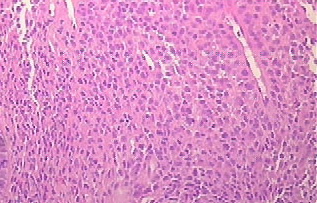

Langerhans cell histiocytosis = كثرة الخلايا الناسجة لانغرهانس